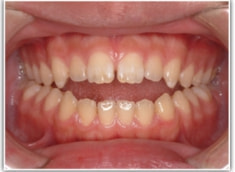

開咬(かいこう:オープンバイト)ケース

治療法:表の矯正(T21ブラケット)

(インプラントアンカーや外科矯正は行わず、エラスティックと機能訓練のみ)

治療前

治療後(2年2ヶ月後)